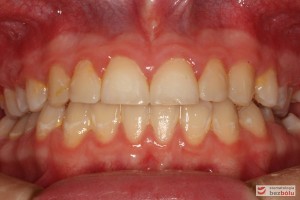

Rodzice zgłosili się z pacjentem celem rutynowej kontroli ortodontycznej. Wykonano OPG i po analizie modeli diagnostycznych stwierdzono brak miejsca dla wyrzynania dolnej prawej piątki stałej oraz zwężenie szczęki wraz z rotacją górnych zębów szóstych. W łuku górnym w pierwszym etapie leczenia zastosowano Rotator, celem odrotowania 6-tek stałych oraz ekspansji łuku w wymiarze poprzecznym. Następnie zamontowano aparat stały metalowy do uszeregowania zębów w łuku. W łuku dolnym miejsce odtwarzano stosując aparat stały i odpowiednią mechanikę leczenia. Leczenie aktywne trwało 3,5 roku, po czym zastosowano terapię retencyjną (retainer stały w żuchwie oraz Płytkę Hawley’a w szczęce).